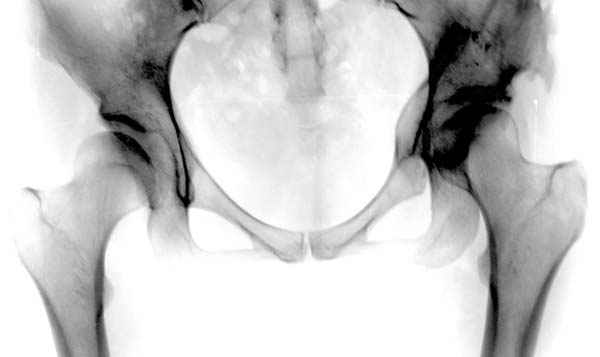

отдаленный результат #12

№ 11-12 послеоперационные, с учетом биомеханики

сустава